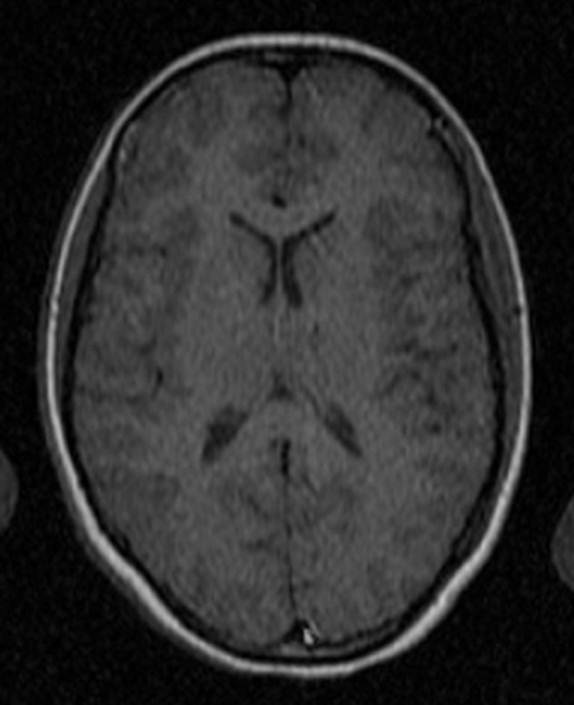

CT: Brain Atrophy

10 Years-Normal Gyri             65 Years-Enlarged Gyri